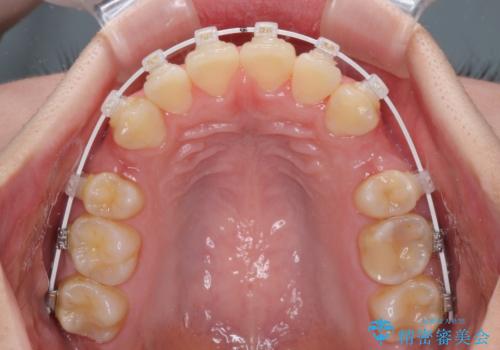

前歯の出っ歯と口の閉じにくさを抜歯矯正で改善 目立たないワイヤー矯正

- 矯正装置

- 審美装置

- 上の前歯の出っ歯とでこぼこの歯並びを気にして来院された患者様です。

口元を積極的に引っ込めるために、上下左右の小臼歯4本を抜歯することとしました。

4本の歯を抜歯したことで、飛び出していた口元が引っ込み、横顔が大きく改善されました。

咬み合わせが悪化することのないようにスペースを閉じていくことができ、比較的スムーズに治療を進めることができました。